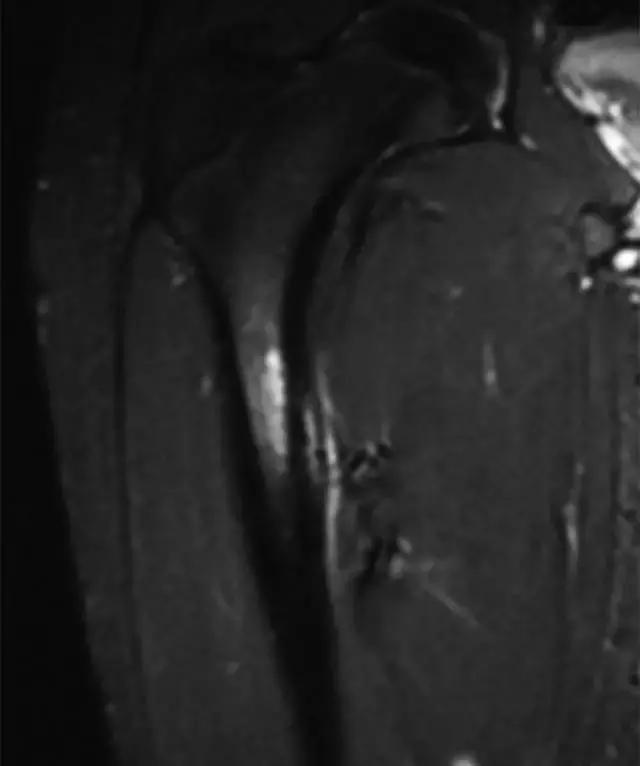

临床诊断可能是具有挑战性的,因为患者经常出现非特异性髋关节和腹股沟疼痛,因此成像通常在这些情况下起关键作用。 射线照片通常是不会发现的,特别是在有骨量减少的患者中,所以应该高度怀疑地看到沿股外侧的任何线性透视或硬化(图11)。 当临床怀疑近端股骨应激损伤时,应强烈考虑MRI,因为相关的骨髓水肿在脂肪抑制T2加权图像上显着,低信号强度骨折线也可能是明显的。

图11〜41岁女性患有糖尿病和外侧股骨颈应力骨折。 左髋前后X线片显示股骨颈侧向(拉伸)方面的局限性皮层破裂(箭头),MRI证实不完全骨折。

股骨干应力性骨折(Femoral Shaft Stress Fracture):

X光片可以揭示沿着股骨内侧轴上的骨膜反应,但研究结果往往正常(图12A)。 放射性核素骨扫描显示该区域的摄取增加,但MRI已成为评估该实体的首选研究[58]。 结果包括骨髓水肿和异常骨膜和皮层信号强度(图12B)。

图12A -14岁男子足球运动员,股骨应力骨折。右髋前后X线片显示沿内侧近端股骨轴的局灶性骨膜炎(箭头),仅在图像边缘部分可见。

图12B,冠状STIR MR图像显示广泛的骨膜反应,内皮和皮质内异常信号强度与发展中的应力骨折相适应。